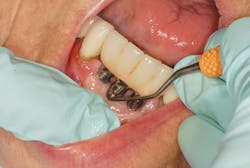

For dental professionals, this means protocols and titanium implant scalers to maintain these rough, porous, and coated implant surfaces for safe and effective peri-implant therapy (Figure 4).

Instrument residue such as cement can become lodged on the implant surface, providing a place for bacterial biofilm to accumulate and can alter the biocompatibility of the titanium surface. This can compromise the long-term osseointegration of the implant.1 Biocompatibility is the key. Use titanium on titanium for safe and effective implant debridement (Figure 6).

The other challenge is to select the proper instruments or tools to debride implants based on implant design, access, and prosthesis. Ideally, use a biocompatible implant scaler made of titanium with Rockwell hardness of less than 30, to avoid leaving any trace elements behind and to not scratch the implants. Use short, horizontal strokes to remove any microbial deposits without leaving any residue behind. See Table 1 for protocol for debridement based on implant design.4,22